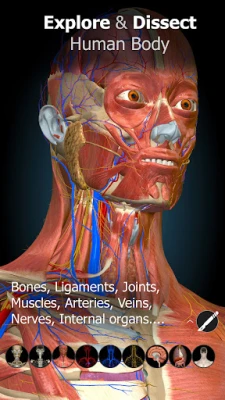

A true and totally 3D app for studying human anatomy, built on an advanced interactive 3D touch interface.

★ Remove structures to reveal the anatomical structures below them.

★ Switch on/off different anatomy systems

★ Bones

★ Ligaments

★ Joints

★ Muscles

★ Circulation (arteries, vein and heart)

★ Central nervous system

★ Peripheral nervous system

★ Sense organs

★ Respiratory

★ Digestive

★ Urinary

★ Reproductive ( both male and female)